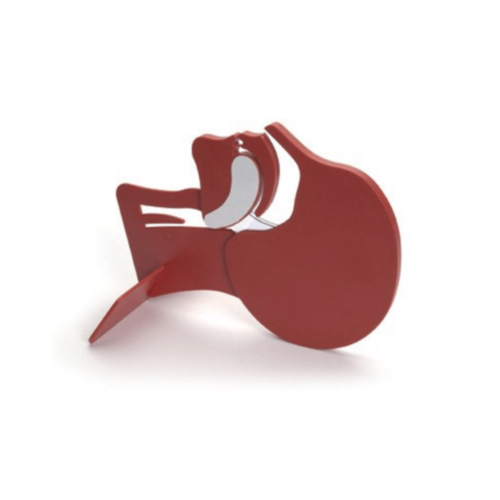

Modèle de tête en coupe

| Nom du produit | Modèle de tête en coupe |

| SKU | 010900 |

Fabricant

Laerdal |

| Poids | 0.4 kgs |